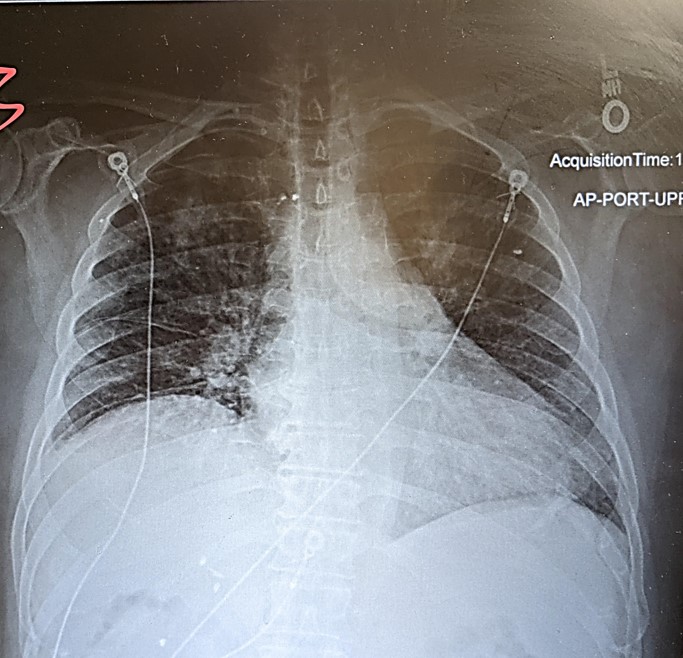

fine inspiratory crackles, egophony, and vocal pectoriloquy. His chest x-ray is shown

below.

On left: patient's chest x-ray showing patchy areas of consolidation and a diffuse increase in interstitial markings (vis-a-vie interstitial fibrosis). These findings were evident during auscultation - diffuse inspiratory crackles (intersitial fibrosis) and egophony and vocal pectoriloquoy (consolidation). This patient had COP-related pulmonary hypertension as indicated by his loud pulmonic closure sound (S2P). On right: chest x-ray and CT scans of other patients with COP.